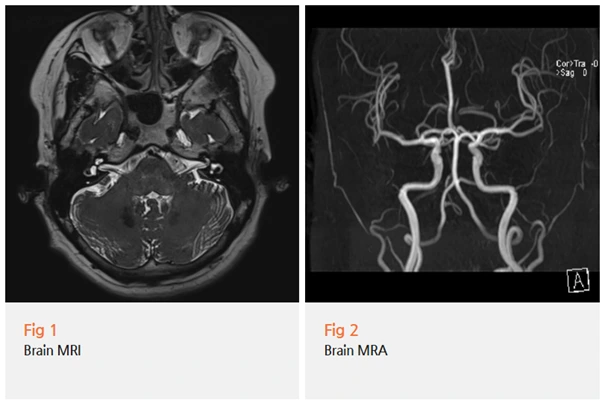

환자분께 당일 뇌 MRI 및 MRA 검사, 그리고 근전도 검사를 권유드렸어요.

이 환자분의 경우, 다행히 혈관성 병변이나 종양,

염증 소견은 없었고 특발성 삼차신경통으로 진단되었어요.

MRI나 MRA로 이 혈관-신경 접촉 여부를 확인할 수 있어요.

뇌 MRI와 MRA를 통해 혈관-신경 압박 여부 및 이차 원인을 확인하고,